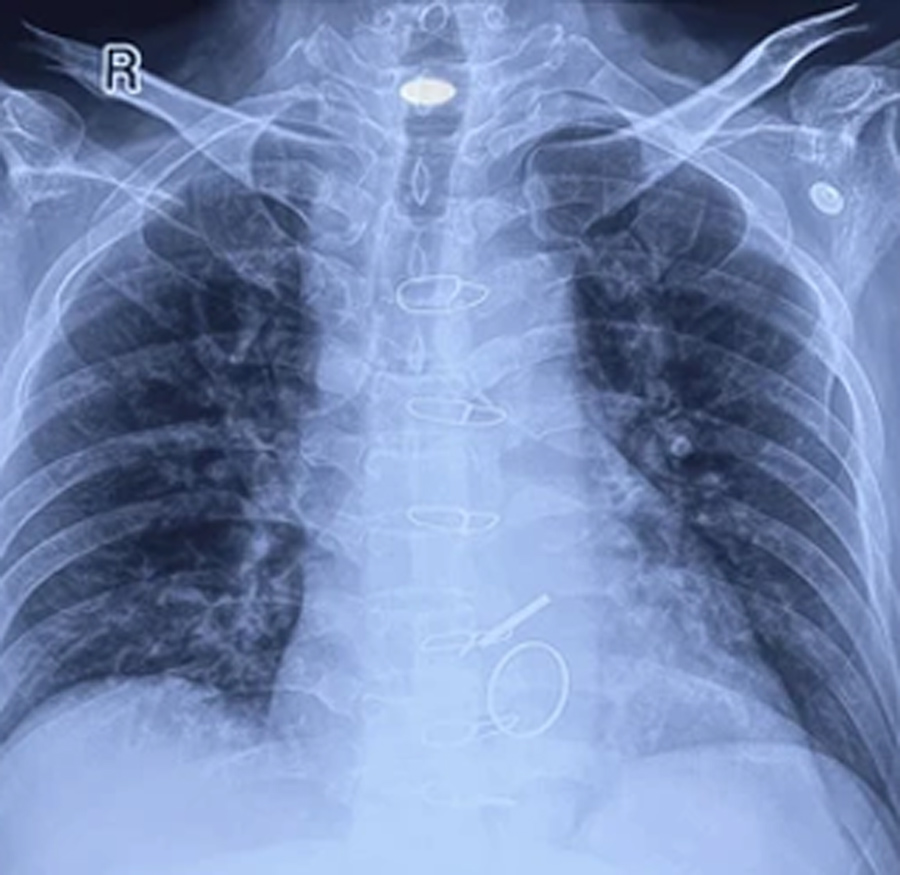

- Chest X-ray: To search for abnormality in the lungs or fluid accumulation